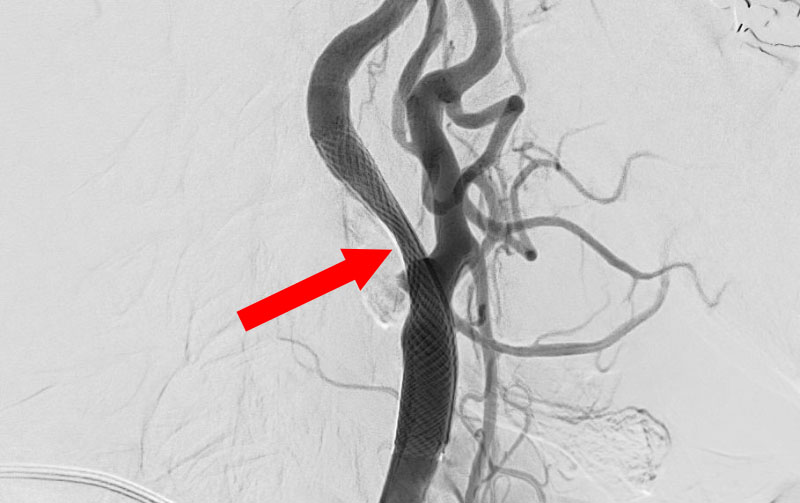

1619

'26年3月11日

左内頚動脈狭窄症

70代

大阪府の病院

手術写真

治療

前

中

後